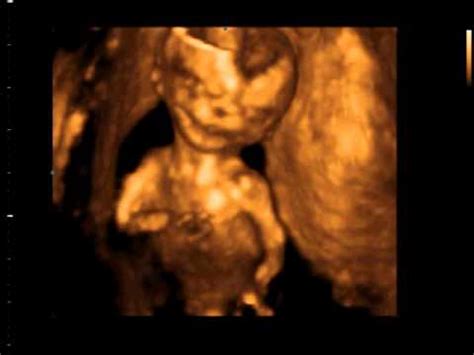

28.03.2011 14 Tydzień Ciąży - YouTube

28.03.2011 14 tydzień ciąży - YouTube www.youtube.com